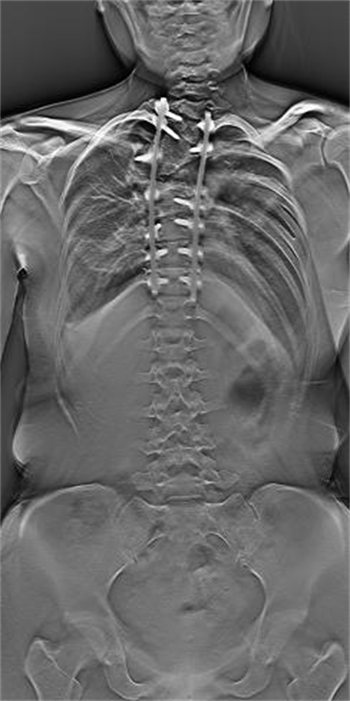

左为二维平片,右为LF-TOMO图像

不仅如此,在图像质控方面,安健科技自主研发的高空间分辨率平板探测器与先进图像处理技术的结合,使得LF-TOMO大范围断层融合技术可以提供高清晰度的断层图像,对于微细骨折的诊断等方面可以提供有效评估。另一方面,LF-TOMO断层融合图像不受体位及金属植入物的影响,无重叠组织结构及金属伪影的干扰,空间分辨率高,为诊断医生提供更多的影像学信息,以提高对病灶的检出率和准确率。因此,LF-TOMO大范围断层融合技术在骨科,对于金属植入物患者的随诊观察有很好的效果,辅助医生完成术前诊断、术中定位以及术后评估。